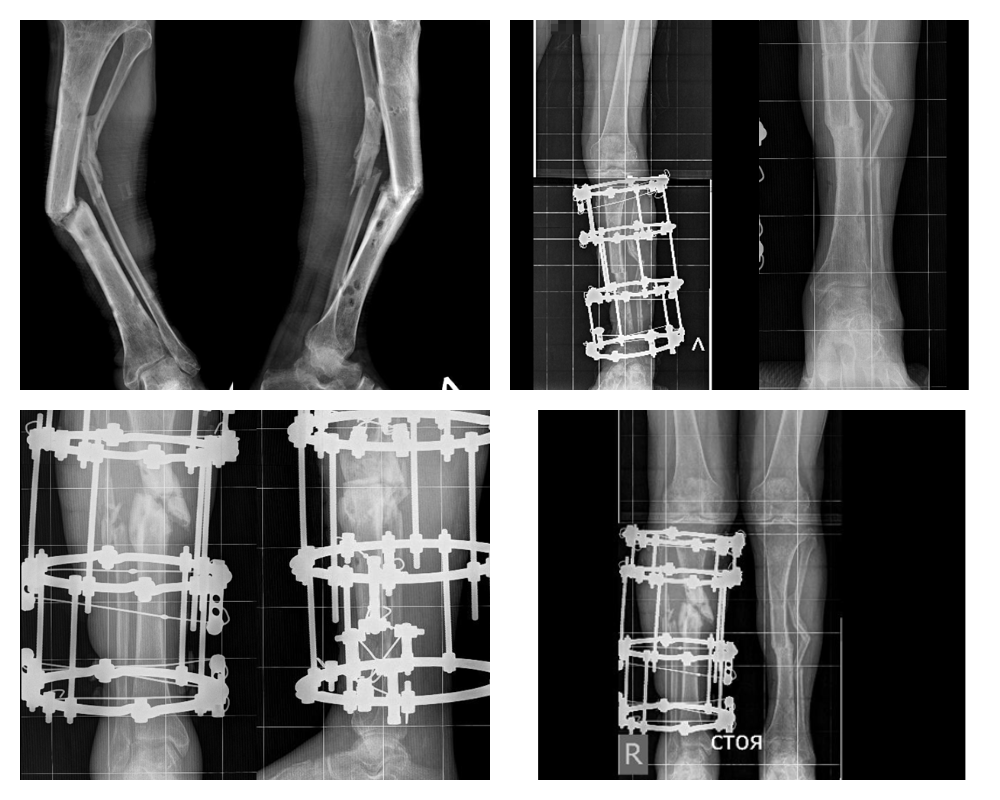

56-летний пациент из Биробиджана получил в дорожной аварии серьезную политравму обеих нижних конечностей. Лечение по месту жительства в 2023 году было связано с первичной хирургической обработкой ран и остеосинтезом голеней аппаратом Илизарова.

Однако лечение не принесло ожидаемых результатов, сращения переломов достичь не удалось. Постепенно сформировалась выраженная деформация обеих голеней более 45 градусов.

Мужчина был вынужден передвигаться на инвалидной коляске. Спустя год после аварии мужчина обратился за помощью в Центр Илизарова. С посттравматическими ложными суставами костей голеней его госпитализировали в Клинику реконструктивной хирургии повреждений нижних конечностей и таза. В отделение №3 накоплен колоссальный опыт лечения посттравматических дефектов и деформаций костей конечностей.

- Первым этапом мы по методу Илизарова исправили деформацию левой голени, достигли консолидации отломков в правильном положении. Вторым этапом уже в этом году выполнили корригирующую остеотомию костей правой голени и остеосинтез аппаратом Илизарова. Мы очень довольны результатом.

Восстановлена биомеханическая ось обеих нижних конечностей, пациент на период фиксации поехал домой, выполняя рекомендации врачей Центра Илизарова под наблюдением местных специалистов, - рассказал заведующий отделением №3 Центра Илизарова, к.м.н. Виталий Нарицын.

В данной ситуации метод Илизарова оказался мощным инструментом в решении сложной операционной задачи в совокупности с многолетним опытом, которым владеют специалисты Центра Илизарова.

Уже после первой операции в Кургане житель Еврейской АО передвигался на своих ногах с помощью костылей, а в после демонтажа аппарата на правой голени, сможет вернуть себе привычные навыки ходьбы без дополнительных средств опоры.